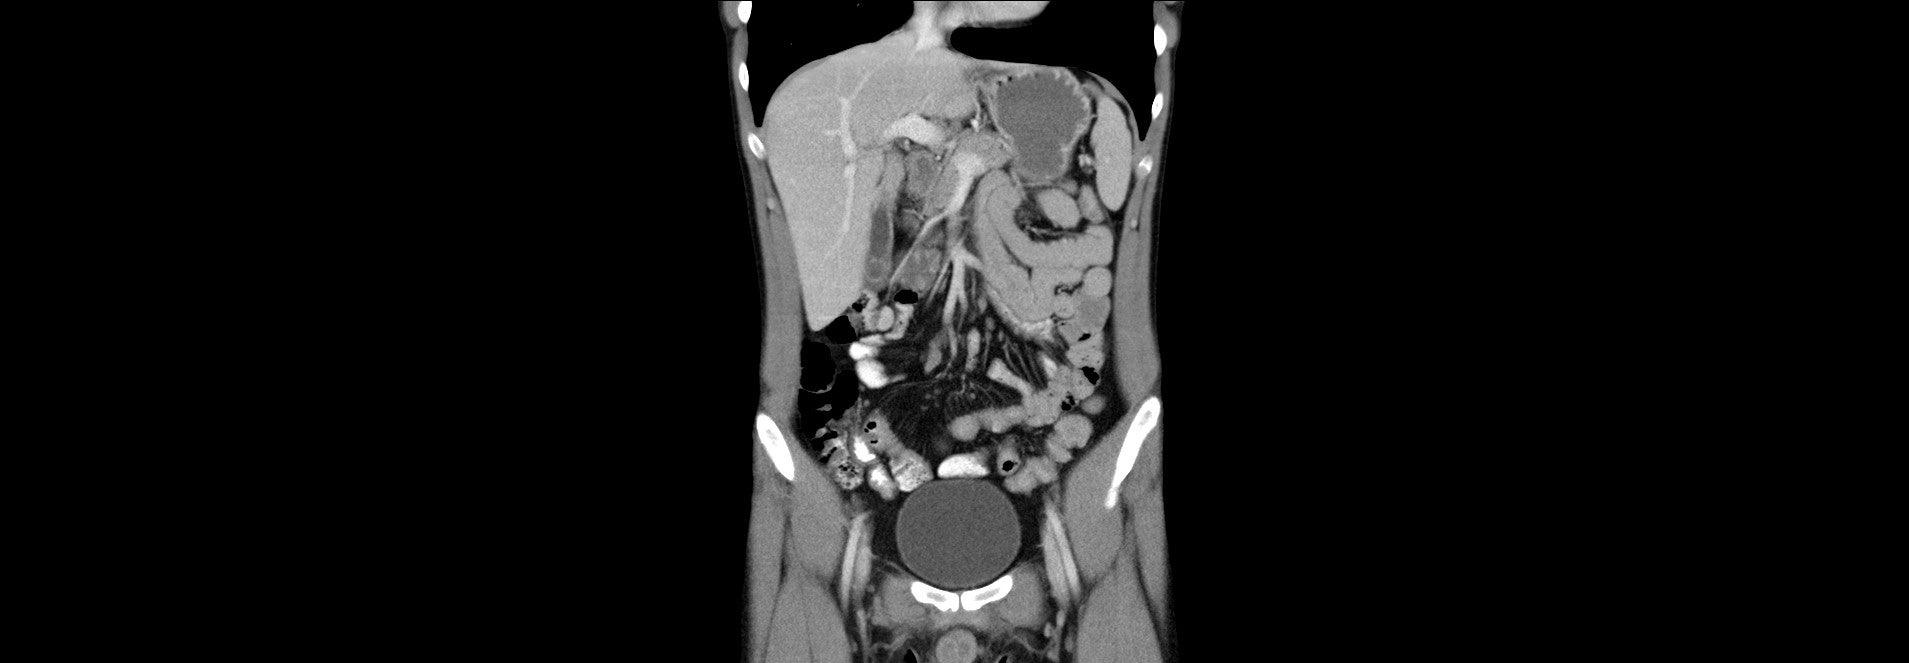

CT břicha ze dne 28.02.2023

Tato kazuistika se zabývá případem mladého muže, nyní ve věku 27 let, u kterého byla v roce 2019 diagnostikována Crohnova nemoc. Primárně byl léčen v té době doporučovanými aminosalicyláty a později azathioprinem, na kterém došlo v únoru 2023 k relapsu onemocnění s multisegmentálním postižením s prestenotickými dilatacemi a zánětlivým pseudotumorem (dle CT vyšetření břicha), které vyžadovalo zavedení enterální výživy a biologické terapie. Pacient byl k další léčbě přeložen na naše pracoviště. V první linii byla použita anti-TNFα terapie infliximabem, na které došlo k postupné úplné regresi aktivity a normalizaci fekálního kalprotektinu. Vzhledem k nutnosti rozsáhle resekce střevních kliček při chirurgickém výkonu s rizikem následného rozvoje syndromu krátkého střeva byl nadále indikován konzervativní postup, pacient byl ale plně realimentován bez pasážovacích potíží.